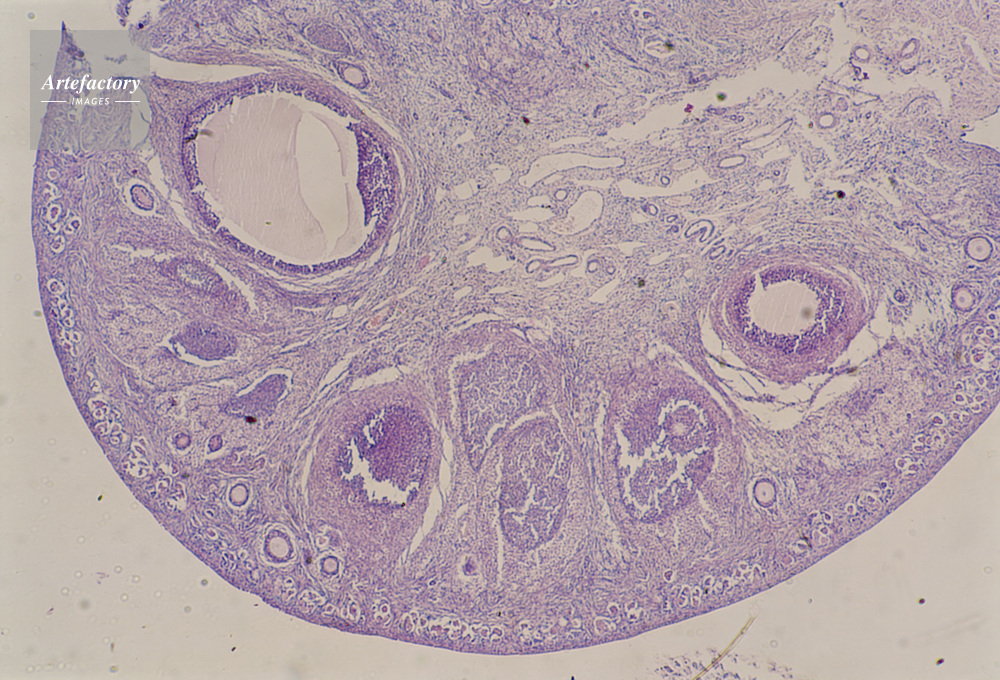

| キャプション | 卵巣,犬,20倍 | 制限事項 | ||

| ソース | ピクセル数 | 5552px × 3776px | ||